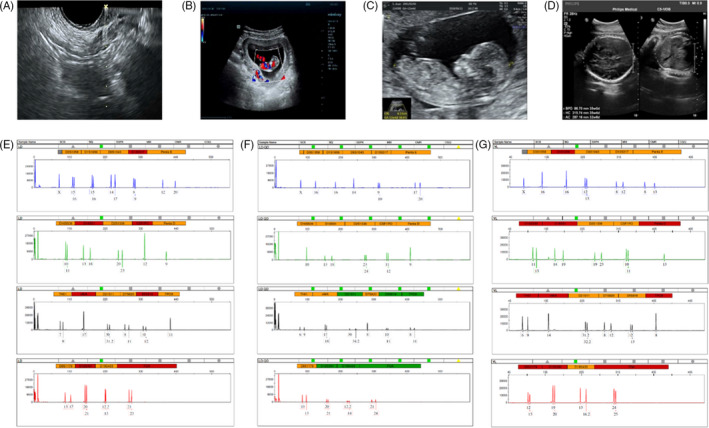

收集了15名接受取卵的患者的基本特征,包括取卵周期、胚胎移植和妊娠次數(shù)。一般來說,四個胎兒沒有出生缺陷,三個胚胎來自ICSI的受精類型,而最后一個是自然受孕的。1例術(shù)中超聲掃描顯示,在經(jīng)陰道超聲(TVUS)引導(dǎo)下,卵巢未見間質(zhì)增生或其他異常卵巢結(jié)構(gòu)(圖2A)。這名婦女在體外受精后成功懷孕,并在第8周進行了基本產(chǎn)前程序的超聲掃描(圖2B),第13周(圖2C) 和第32周 (圖二維) 顯示正常的胎兒發(fā)育。微衛(wèi)星位點分析顯示,胎兒(圖2F)與母親有遺傳關(guān)系(圖2E) 供體UCMSC以外的其他人(圖2G)。